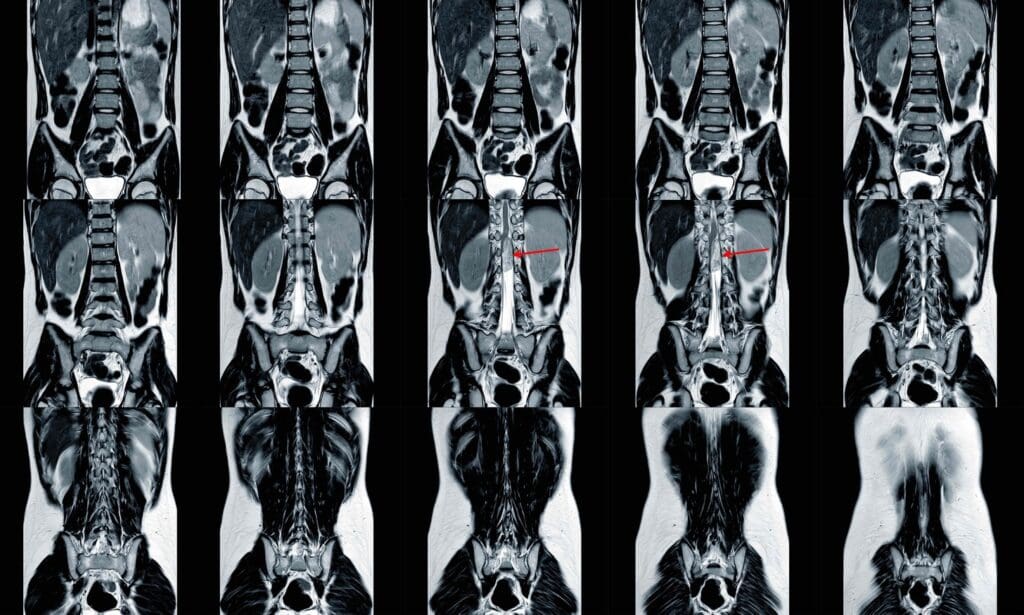

Imaging Technologies: X-rays, CT, MRI, and Bone Scans

Imaging is key in spotting bone metastases. We use different tools to see how much of the bone is affected.

- X-rays: Good for finding big bone problems and breaks.

- CT (Computed Tomography) scans: Show detailed bone pictures and find small issues.

- MRI (Magnetic Resonance Imaging): Very good at finding bone marrow and soft tissue problems.

- Bone scans: Use a tiny bit of radioactive stuff to show active bone areas, which might have metastases.